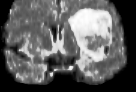

We present results obtained on the MICCAI multi-modal Brain Tumor Segmentation (BRATS) dataset [49]. This challenging dataset contains real and simulated patient data, with overall poor resolution and large variation of tumor shape and position. For both types, high grade (HG) and low grade (LG) tumors are provided with four modalities: T1, contrast enhanced T1 (T1C), T2, and FLAIR. Overall, there are 20 and 10 real patient data with respectively HG and LG tumors, and 25 images for both HG and LG simulated tumor data. We use the same SPM parameters as in Section V-B, taking a multi-modal histogram, containing the levels of gray intensity on all MRI modalities as descriptor for superpatch matching, and performing the regularization (8) at the pixel scale to compare with pixel-wise ground truths. Each subject is segmented by the remaining of its type in a leave-one-out procedure.

In Fig. 12, we show several tumor segmentation results for all data types.

In Table II, we compare results obtained using different descriptor structures:

patch-based [48], superpixel-based [54],

and superpatch-based (= pixels).

We use the Dice coefficient [55] as evaluation metric,

measuring the overlap between the automatically segmented structure and the ground truth.

The superpixel-based approach

appears very limited since it fails at capturing the tumor context and their location in other images.

Regular patches are also limited in this context, due to the variations in the structure shapes.

Superpatches provide a robust descriptor, since they follow image intensities and capture the superpixel neighborhood,

leading to more accurate segmentation.

These experiments demonstrate that superpatches within the SPM framework provide fast and accurate segmentation results

even on non-registered multi-modal images with poor resolution.